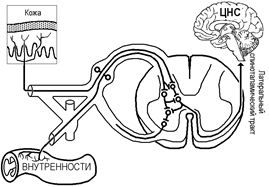

Каузалгию можно объяснить с позиций теории воротного контроля: При этом увеличивается поток импульсов к нейронам задних рогов спинного мозга — «ворота открываются». В спинном мозге или выше появляется генератор патологически усиленного возбуждения, образование которого обусловлено растормаживанием группы нейронов в связи с нарушением внешнего аппарата контроля, который локализован в поврежденной структуре (рис.).

Рис.. Объяснение каузалгии по теории воротного контроля.

Одна из причин отражённой боли — конвергенция ноцицептивных афферентов от кожи и внутренностей на одних и тех же клетках, дающих начало восходящим ноцицептивным трактам (рис.).

Рис.. Пути возникновения отраженной боли. Некоторые из ноцицептивных афферентов от внутренних органов оканчиваются в заднем роге на тех же нейронах, что и ноцицептивные афференты от кожи.

Вторая причина-ветвление первичных ноцицептивных афферентов в спинальных нервах с образованием двух или более коллатералей, так что одно волокно иннервирует и поверхностную, и внутреннюю структуры (рис.).

Рис.. Пути возникновения отраженной боли. В некоторых случаях ветви одного и того же ноцицептивного афферента иннервируют и поверхностную, и глубокую ткани.

В обоих случаях возбуждение центральных ноцицептивных нейронов воспринимается как периферическая боль, возможно, потому, что такая интерпретация обычно соответствует прошлому опыту.

Другое следствие центральных конвергенции и дивергенции ноцицептивных афферентов, показанное на рис., — возможность развития в затронутом дерматоме гиперпатии или гиперестезии (см. ниже) кожи. Причина в усилении возбудимости спинальных интернейронов ноцицептивными импульсами из глубоких тканей, поэтому стимул, действующий на кожу, вызывает центральную активность, превышающую нормальную. Следует иметь в виду, что невралгия также может создавать впечатление отраженной боли или включать в себя отраженный компонент.